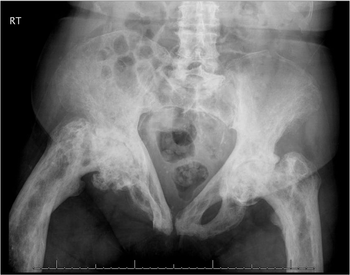

Whatever is causing this woman’s hip pain, her x-ray film looks quite severe. The diagnosis was correct 40 years ago, but it couldn’t be treated effectively then. What’s the problem?